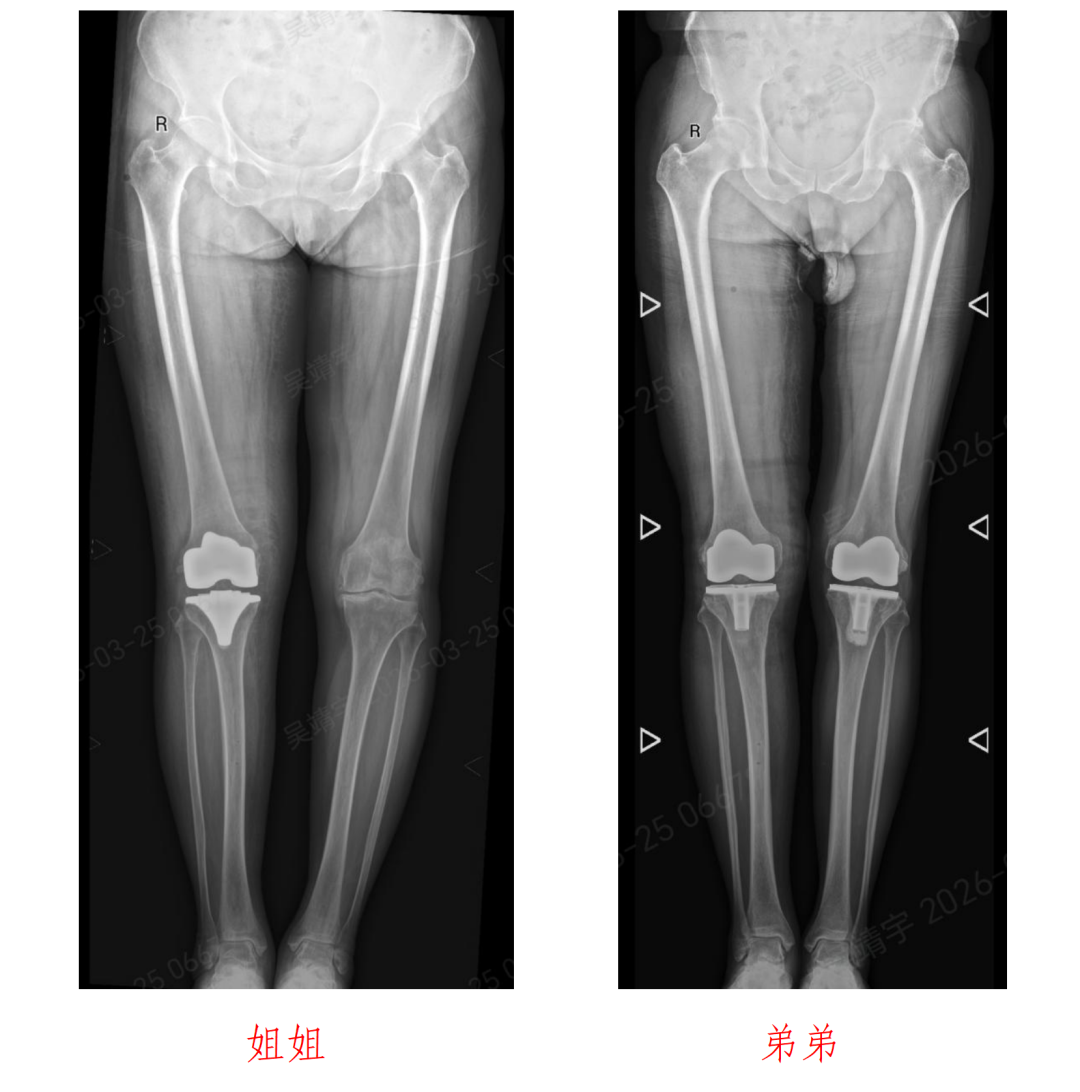

72岁的姐姐沙女士与64岁的弟弟沙先生,多年饱受膝关节病痛困扰。

近日,北京积水潭医院郑州医院关节外科主任杨锴、副主任医师吴靖宇采用骨科手术机器人辅助全膝关节置换术,成功为这对姐弟患者实施右侧人工全膝关节置换手术。

术后一周,姐弟二人膝关节功能恢复良好,疼痛症状显著缓解,均可自主下床活动,诊疗效果获得患者认可。

沙女士姐弟二人多年来均被严重的膝关节骨性关节炎困扰,膝关节疼痛、肿胀、活动受限,日常行走、上下楼梯都十分困难,严重影响生活质量。随着年龄增长,病情愈发严重,保守治疗早已无法缓解症状,都希望可以使用手术改善生活质量。

手术过程十分顺利,姐弟二人的右侧全膝关节置换手术均圆满完成。术后,医院快速康复(ERAS)护理团队同步介入,为姐弟俩制定专属康复计划,开展个性化功能锻炼指导、疼痛管理、营养支持等全方位护理。